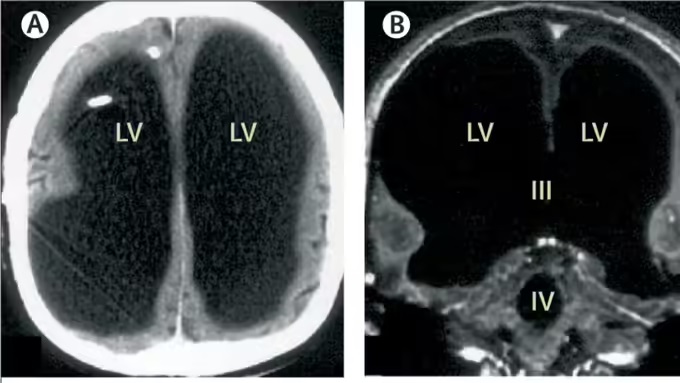

‘द लैंसेट’ में प्रकाशित इस केस रिपोर्ट के अनुसार, उस व्यक्ति के सिर में दिमाग की जगह तरल पदार्थ भरा हुआ था, और केवल एक पतली परत में ब्रेन टिश्यू बचा था। इसे हाइड्रोसेफेलस नामक स्थिति कहा जाता है, जिसमें दिमाग के अंदर तरल पदार्थ (cerebrospinal fluid) जमा हो जाता है।

रिपोर्ट के अनुसार, जब वह व्यक्ति सिर्फ 6 महीने का था, तब उसे पोस्टनैटल हाइड्रोसेफेलस हुआ था, जिसके इलाज के लिए उसके सिर में शंट सर्जरी की गई थी। 14 साल की उम्र में भी उसे पैर में कमजोरी और चलने में परेशानी महसूस हुई थी, लेकिन इलाज के बाद वह पूरी तरह ठीक हो गया। बाद में 44 साल की उम्र में दोबारा पैर में कमजोरी आने पर उसका CT और MRI स्कैन किया गया, और तब पता चला कि उसका लगभग पूरा दिमाग तरल पदार्थ से भरा हुआ है।